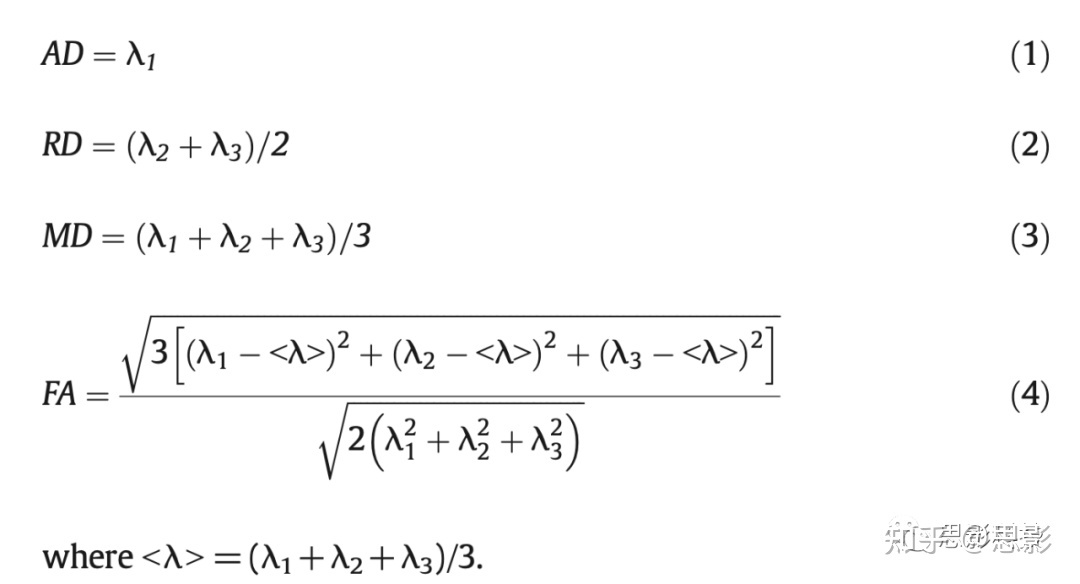

ROIs

本研究考虑了白质中的48个感兴趣区域(ROIs),包括相同解剖结构的双侧区域(图1)。在标准MNI空间中定义ROIs,并将所有扩散度量图都非线性转换到标准空间进行统计分析。使用FSL配准工具FLIRT和FNIRT将个体受试者的FA map非线性地配准到标准空间FA图像(FMRIB58_FA_1mm)上。将相同的变换矩阵应用于其他扩散度量。为了避免灰质和脑脊液的部分体积效应,通过将白质图谱、Johns Hopkins University(JHU)ICBM-DTI-81与所有受试者创建的共同白质骨架相交叉,白质ROIs具有高度选择性(图1)。JHU的白质图谱是在FSL中提供的,而白质骨架是使用FSL在其基于纤维束示踪的空间统计(TBSS)工具箱中提供的命令创建。ROIs和体素数的定义如表1所示。

图1 通过将平均FA骨架和白质图谱相交,在标准MNI空间中定义了48个白质ROIs。

平均FA骨架由47名受试者的TBSS命令创建,白质图谱由FSL的JHU ICBM-DTI-81提供。下图显示了标准MNI空间中覆盖在平均FA图上的48个ROIs。表1中列出了ROIs的首字母缩写词,并带有匹配的颜色。